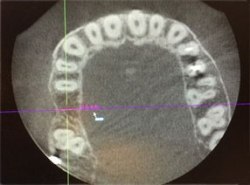

植牙配合鼻竇增高

電腦斷層